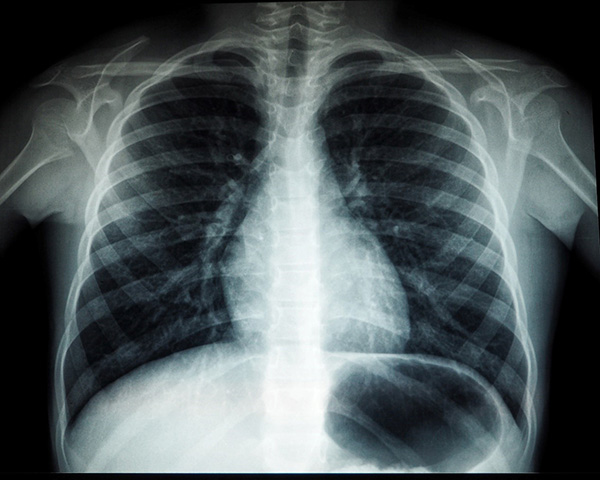

由艾伯塔大学的计算科学团队和衍生公司MEDO的成员发表的一项新研究表明,一种新的深度学习模型可以更快、更准确地从医学扫描图中识别疾病。这个突破性的模型是该大学科学学院的一个研究团队的成果。

深度学习是人工智能子领域机器学习中的一种技术,作为一种计算机算法,它可以从大量的数据中找到合适的模式,生成可用于进行预测的模型。这些模型通过需要经过十万到百万级的实例学习,才能达到最佳效果。但在医学领域,出于隐私和保密等原因,研究人员通常只能访问几百张医学扫描图像,这无疑是医学诊断领域一个独特的挑战。

提升性能的另一个方法是,通过医学专家间接提供的数据,对医学图像算法进行训练。这种方法允许算法从扫描图像中学习表征各种疾病的模式,从而使其能够预测新患者的扫描图像结果是否健康。

“我们的方法既提高了模型诊断的准确性,又为其预测提供了有意义的可信度,从而得以估计扫描图像存在疾病的概率,”Vega说。

“通过这项研究,我们希望为放射科医生提供更好的工具,让他们的工作更轻松、快捷,和高效。我们也面临着医务人员稀缺的问题,这在发展中国家更加严重。我们希望开发出的模型让医学专家能做出更好的决定。”